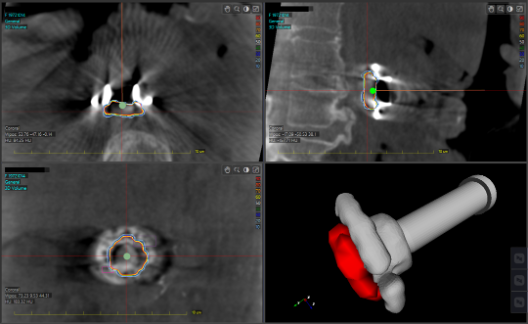

天津醫(yī)科大學(xué)腫瘤醫(yī)院近日完成的手術(shù),在全球首先實(shí)現(xiàn)了移動(dòng)式CT圖像引導(dǎo)的胰腺癌術(shù)中精準(zhǔn)放療。由于患者腫瘤位置靠近重要血管,治療團(tuán)隊(duì)在術(shù)中將腫瘤完整切除后,利用醫(yī)療移動(dòng)式C臂CT系統(tǒng)Cios Spin術(shù)中影像輔助實(shí)施放療手術(shù)方案:

利用先進(jìn)的術(shù)中CT設(shè)備以及獨(dú)有的去金屬偽影技術(shù),在30秒內(nèi)快速準(zhǔn)確地采集患者術(shù)中瘤床區(qū)域高質(zhì)量圖像

基于術(shù)中實(shí)時(shí)CT,對(duì)瘤床和復(fù)發(fā)風(fēng)險(xiǎn)較高區(qū)域快速勾畫,計(jì)算并得到三維圖像和劑量分布

根據(jù)實(shí)時(shí)圖像進(jìn)行準(zhǔn)確、快速的劑量疊加

術(shù)中放療施用器根據(jù)治療計(jì)劃和患者術(shù)中圖像進(jìn)行準(zhǔn)確配準(zhǔn)